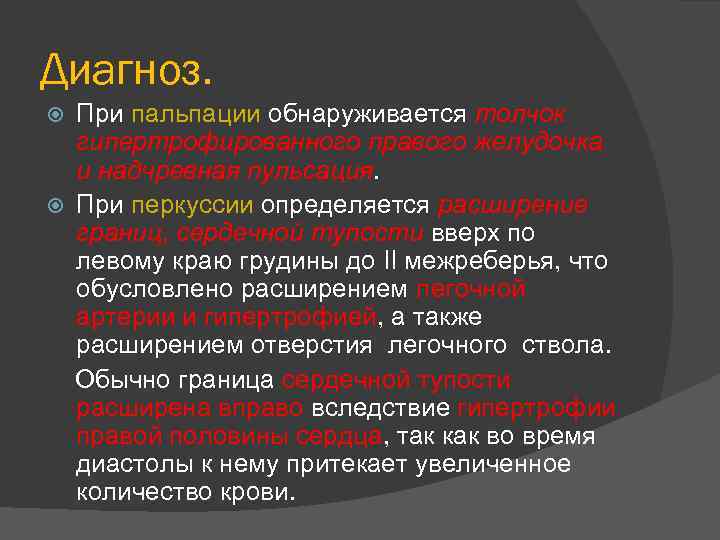

Диагноз. При пальпации обнаруживается толчок гипертрофированного правого желудочка и надчревная пульсация. При перкуссии определяется расширение границ, сердечной тупости вверх по левому краю грудины до II межреберья, что обусловлено расширением легочной артерии и гипертрофией, а также расширением отверстия легочного ствола. Обычно граница сердечной тупости расширена вправо вследствие гипертрофии правой половины сердца, так как во время диастолы к нему притекает увеличенное количество крови.